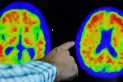

Este año, la campaña "Nunca es demasiado pronto, Nunca es demasiado tarde" se centra en los factores de riesgo y en el papel crucial que desempeña su reducción para evitar, retrasar o incluso prevenir la enfermedad de Alzheimer y otras formas de demencia.

Y resalta que "dado que el número de personas con demencia se triplicará de aquí a 2050, nunca ha sido tan importante reconocer los factores de riesgo asociados a la demencia y tomar medidas proactivas para reducirlos. Además de luchar contra el estigma que rodea a la demencia y promover una mejor comprensión de la enfermedad, podemos trabajar juntos para reducir el impacto de la demencia en las personas, las familias y la sociedad en su conjunto".